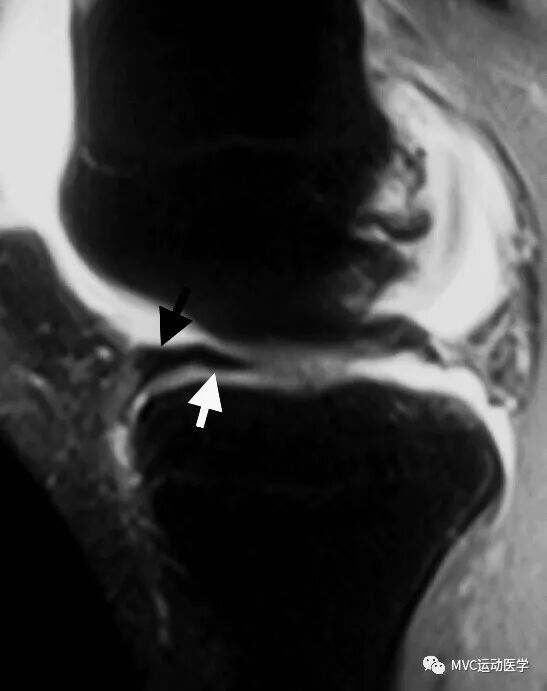

十一、半月板前角假性肥大(前角翻转)

常见于外侧半月板桶柄样撕裂。半月板后角消失,离断的半月板后角向前方移位,位于前角后方,中间填充关节液,形成半月板前角假性肥大。

半月板前角假性肥大举例

黑色箭头所指为半月板前角,白色箭头所指为撕裂的半月板向前移位